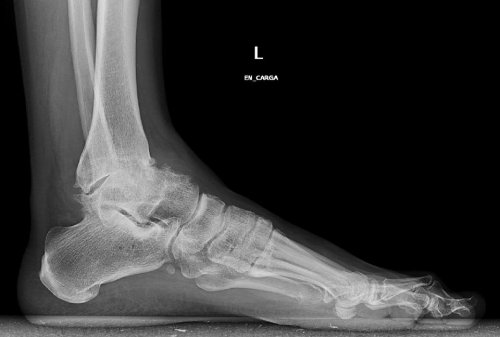

Denne form for gigt er forårsaget af progressiv slid på ankelledets brusk. Det er almindeligt, at vores ankler bliver stive og udvikler deformiteter, som vi ældes.

Klassiske bensporer kan også forekomme, hvilket gør det til en meget smertefuld, såvel som bevægelses begrænsende tilstand.

- Traumatologer siger også, at der er en særlig årsag til denne tilstand: deformation af ankelen selv. Nogle gange er vi mere tilbøjelige til at udvikle slidgigt over tid bare ved at have flade fødder.